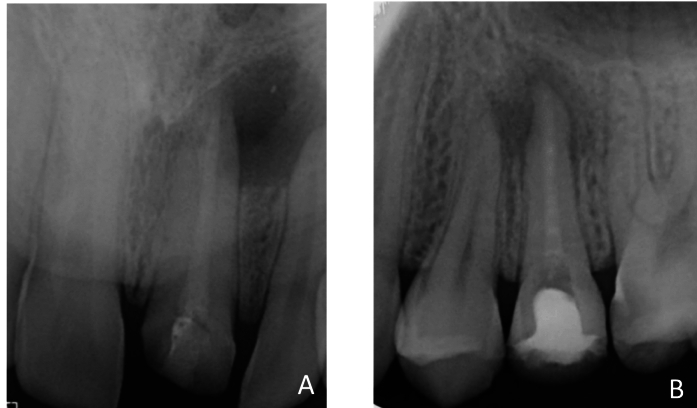

本研究旨在探讨硅酸三钙和氢氧化钙基肛管内敷对无症状根尖周围病变中核因子κ B配体(RANKL)、骨保护素(OPG)、肿瘤坏死因子-α (TNF-α)、前列腺素- e2 (PGE-2)和转化生长因子-β (TGF-β)释放的影响。将纳入研究的60例患者根据肛管内敷料情况随机分为两组。将杜胶从根管中去除后,用三张纸锥从根尖组织中提取RANKL、OPG、TNF-α、PGE-2和TGF-β样品,并将选择的敷料放入根管中。在第二次预约中,取出敷料,并使用相同的方法采集第二次样本。采用酶联免疫吸附试验检测治疗前后RANKL、OPG、TNF-α、PGE-2和TGF-β水平。数据分析采用t检验、Mann-Whitney U检验、Wilcoxon检验、Fisher-Freeman-Halton检验和Path分析。在人口统计学变量(年龄、性别、牙齿区域、吸烟情况)方面,组间差异无统计学意义(p < 0.05)。两组患者治疗前后RANKL/OPG、TNF-α、PGE-2、TGF-β水平比较,差异均有统计学意义(p 0.05)。硅酸三钙基管内敷料可有效降低根尖周围病变的RANKL/OPG、TNF-α、PGE-2和TGF-β水平,但氢氧化钙基管内敷料可降低RANKL/OPG、TNF-α和TGF-β水平的百分比更高。两种药物对PGE-2水平的影响相似。该研究于2024年3月12日在临床试验数据库中注册(https://www.clinicaltrials.gov)。注册号:NCT06307678。